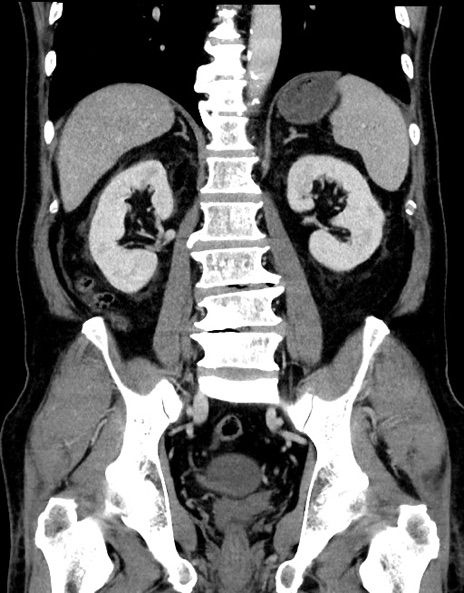

症例15(冠状断像)

【症例】70歳代男性

【主訴】腹痛

【現病歴】今朝から腹痛あり。全体的に痛い。特に左上の方。排ガスが今日はない。冷や汗が出る。

【既往歴】直腸癌術後

【身体所見】左側腹部〜上腹部に圧痛あり。腹膜刺激症状明らかなではない。軽度反跳痛。左下腹部に術後瘢痕あり。

【データ】WBC 7700、CRP 0.02